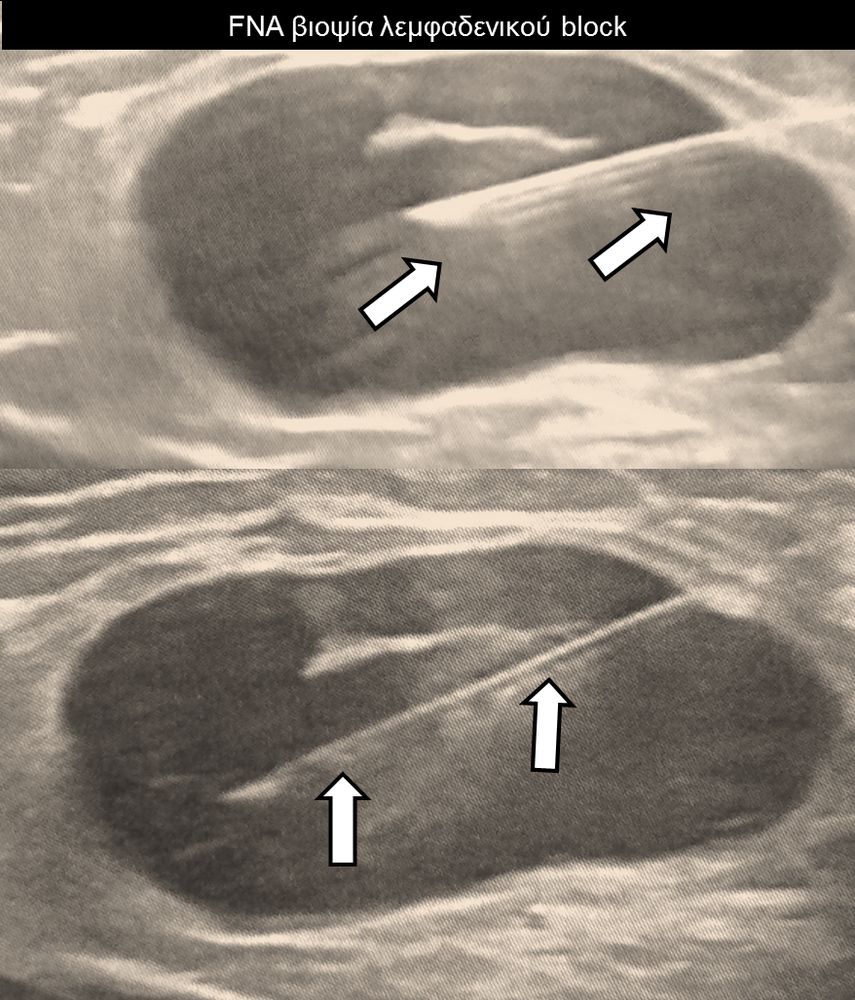

Η διαδερμική βιοψία είναι μία ελάχιστα επεμβατική μέθοδος λήψης υλικού από τον όγκο για κυτταρολογική και ιστολογική εξέταση, από εστιακές αλλοιώσεις του ήπατος, πνεύμονα, νεφρού κλπ. Συστήνεται από τον κλινικό ιατρό ανάλογα με το είδος και το μέγεθος της βλάβης και πραγματοποιείται με ασφάλεια από επεμβατικό ακτινολόγο με την καθοδήγηση αξονικού τομογράφου ή υπερήχων. Στη σύγχρονη ογκολογική θεραπεία όπου γίνεται προσπάθεια καταπολέμησης του καρκίνου σε μοριακό επίπεδο κρίνεται αναγκαία η ακριβής ιστολογική ταυτοποίηση του όγκου ώστε να εφαρμοσθεί εξατομικευμένη θεραπεία για το βέλτιστο αποτέλεσμα. Οι κατευθυνόμενες βιοψίες στοχευουν στο να παρέχουν στον κλινικό ογκολόγο το απαραίτο ιστοπαθολογικό υλικό που θα του επιτρέψει να εφαρμόσει την κατάλληλη θεραπεία για τον ογκολογικό ασθενή.